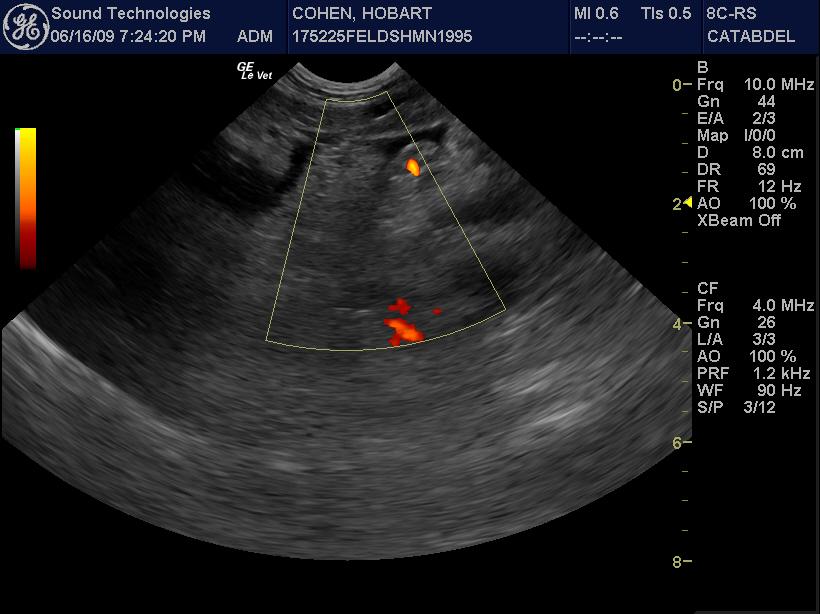

An 8-year-old MN DSH with history of hairballs (currently on Laxatone therapy), was presented for evaluation of vomiting. Abnormalities on physical examination were listlessness and mild dehydration. CBC showed leukocytosis, neutrophilia, basophilia, high MCHC, and elevated MCH. On blood chemistry hyperalbuminemia, elevated ALP and ALT activity, hypercholesterolemia, mild hyperglycemia, slight hypokalemia, and hyperbilirubinemia were evident. Blood gas analysis showed alkalosis with decreased HCO3, PCO2, and TCO2. T-4 was within normal range.

An 8-year-old MN DSH with history of hairballs (currently on Laxatone therapy), was presented for evaluation of vomiting. Abnormalities on physical examination were listlessness and mild dehydration. CBC showed leukocytosis, neutrophilia, basophilia, high MCHC, and elevated MCH. On blood chemistry hyperalbuminemia, elevated ALP and ALT activity, hypercholesterolemia, mild hyperglycemia, slight hypokalemia, and hyperbilirubinemia were evident. Blood gas analysis showed alkalosis with decreased HCO3, PCO2, and TCO2. T-4 was within normal range.

US-guided FNA of the pancreas revealed suppurative pancreatitis

Type of Imaging : Ultrasound